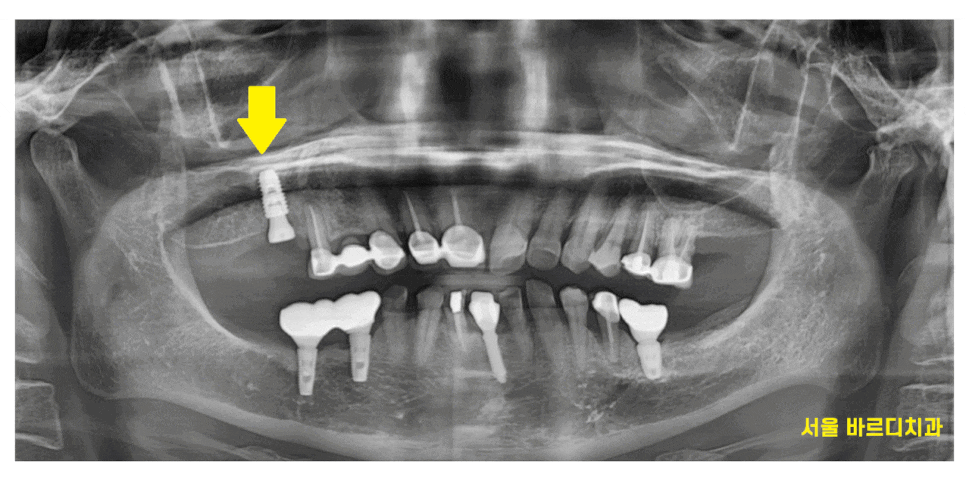

암사동 치과를 방문해주신 환자분입니다.

처음 방문하셨을 때

어금니 곳곳이 빠지신채로 오셨습니다.

구강내를 직접 보았더니

어금니가 몇개 결손 되었어도

양쪽으로 끝에 치아가 빠져서

위 아래 맞물리는 치아끼리 없어서

1개의 임플란트만 진행하면 되었습니다.